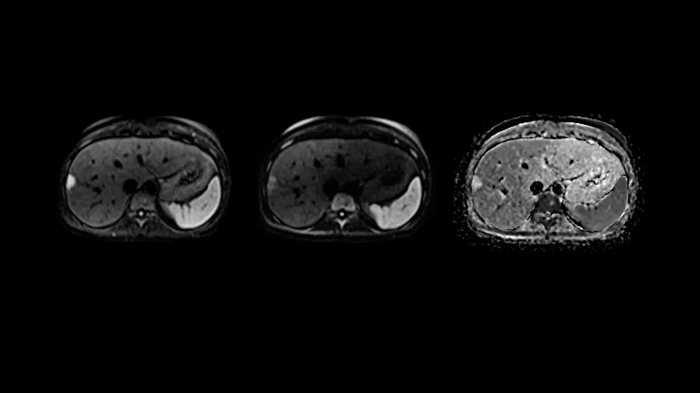

T1 VIBE Dixon with CAIPIRINHA

Benefit from Siemens Healthineers’ dedicated CAIPIRINHA acceleration to gain a complete abdominal volume within a single breath-hold. The Dixon technique offers outstanding fat-water separation for a flawless representation of the abdominal anatomy.

• Contour L Coil

• Spine Coil

80 cm bore MAGNETOM Free.Max

Image Courtesy: University Hospital Erlangen, Germany | Image-ID: 4aaaa0458

Body diffusion imaging

Outstanding quality diffusion imaging for comprehensive abdominal MR capabilities.

Image Courtesy: University Hospital Erlangen, Germany | Image-ID: 4aaaa0339